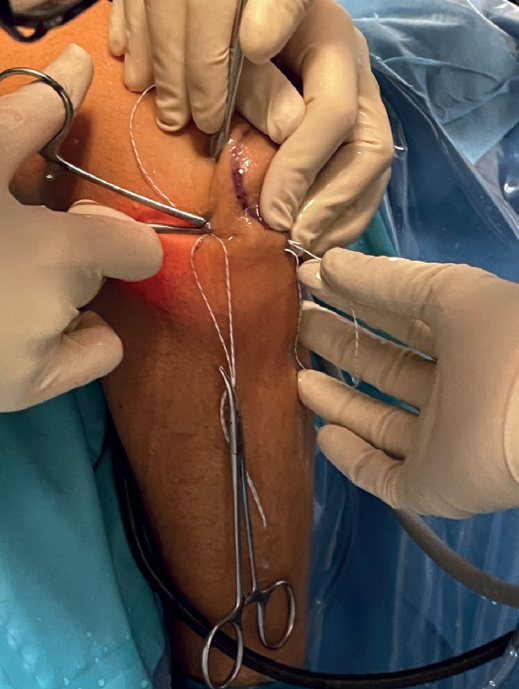

At this point we will have two sutures exiting through the soft spot; we will knot them together (Figure 4) to recover them by pulling on the suture located at the origin of the LCL. In this way we will have a single intra-articular suture extending from the insertion to the origin of the LCL, exiting through the skin in both places (Figure 5).

Another suture of the same type is taken folded in half and transported intra-articular using the previous suture, so that, by making a cut at the looped end, we have two suture strands at both skin exit points (Figure 6).

Using a straight mosquito, one end of the suture is retrieved subcutaneously at the soft spot from the origin of the LCL, and the other end is retrieved from the insertion of the LCL (Figure 7).

The subcutaneous pass is then made again with the other piece of suture.